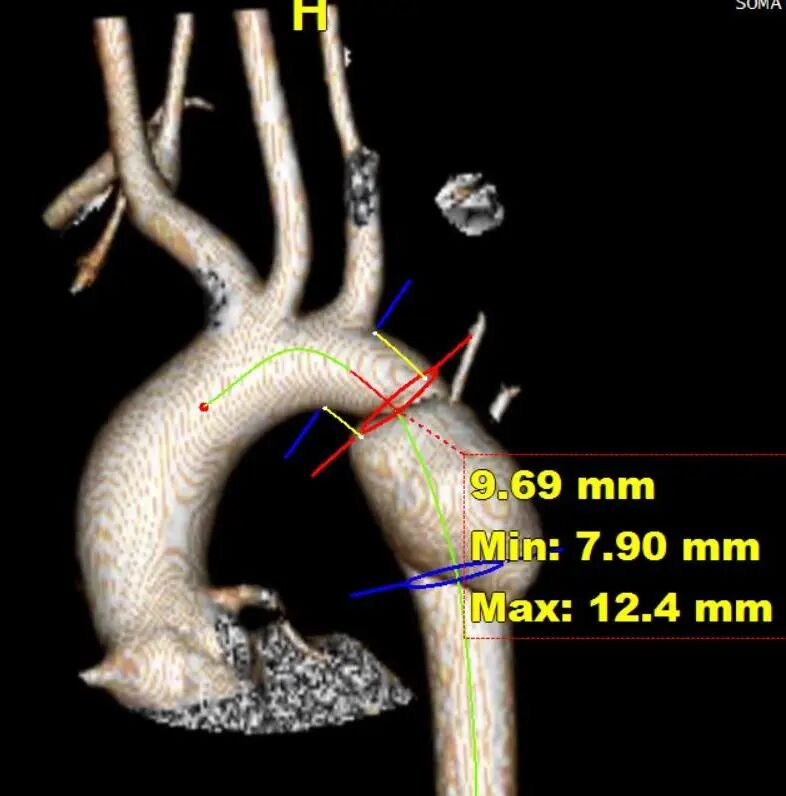

青海省心脑血管病专科医院收治了一名年仅15岁的女孩,因意外高空坠落导致主动脉夹层,患者主动脉直径仅14.7-17.6mm,在评估解剖后植入直径最小的21mm的GORE® TAG® 可主动调控胸主动脉覆膜支架(以下简称CADS支架)精准释放,完美隔绝。

血管直径

CADS支架最小直径为21mm,长度10cm,其宽泛的放大率窗口不仅适合现在患者的主动脉脉直径,也能适应患者随着年纪增大而逐渐增粗的主动脉直径。其独特的分段式释放方式,可以实现近远端精准定位,增加手术的可控性和安全性。